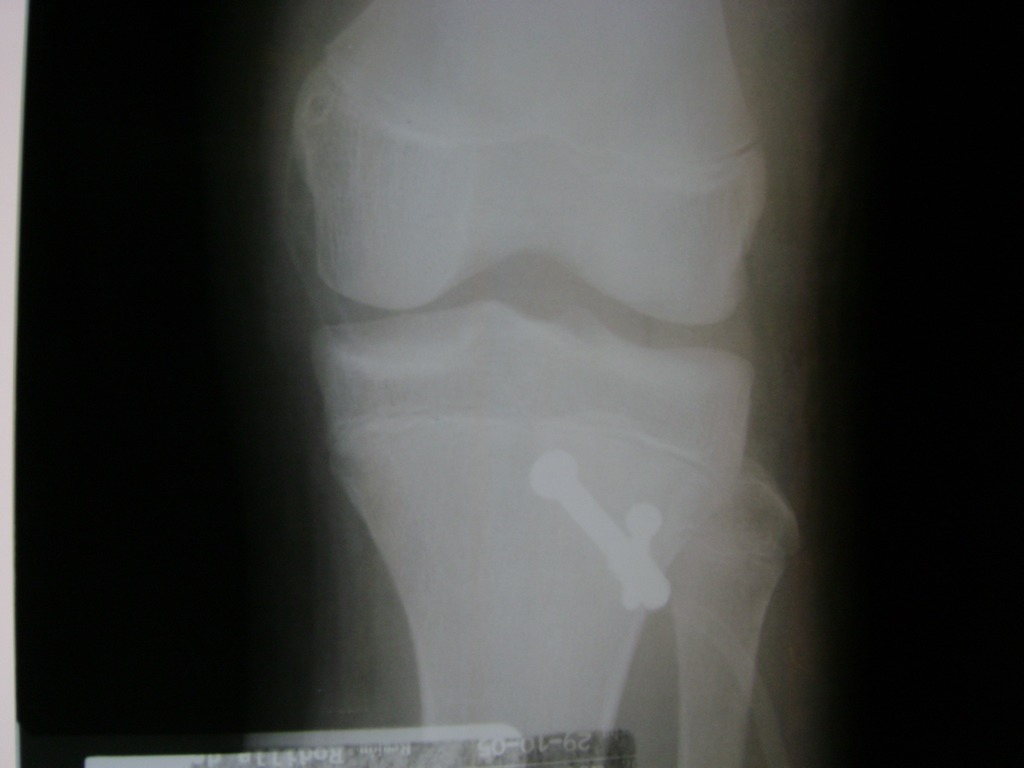

Cirugías de Peroné y Tibia

La artroscopia de rodilla es un cirugía en el cual la estructura interna de la articulación es examinada ya sea para realizar un diagnostico o para realizar un tratamiento, este procedimiento se realiza utilizando un instrumento parecido a un pequeño tubo llamado artroscopio.